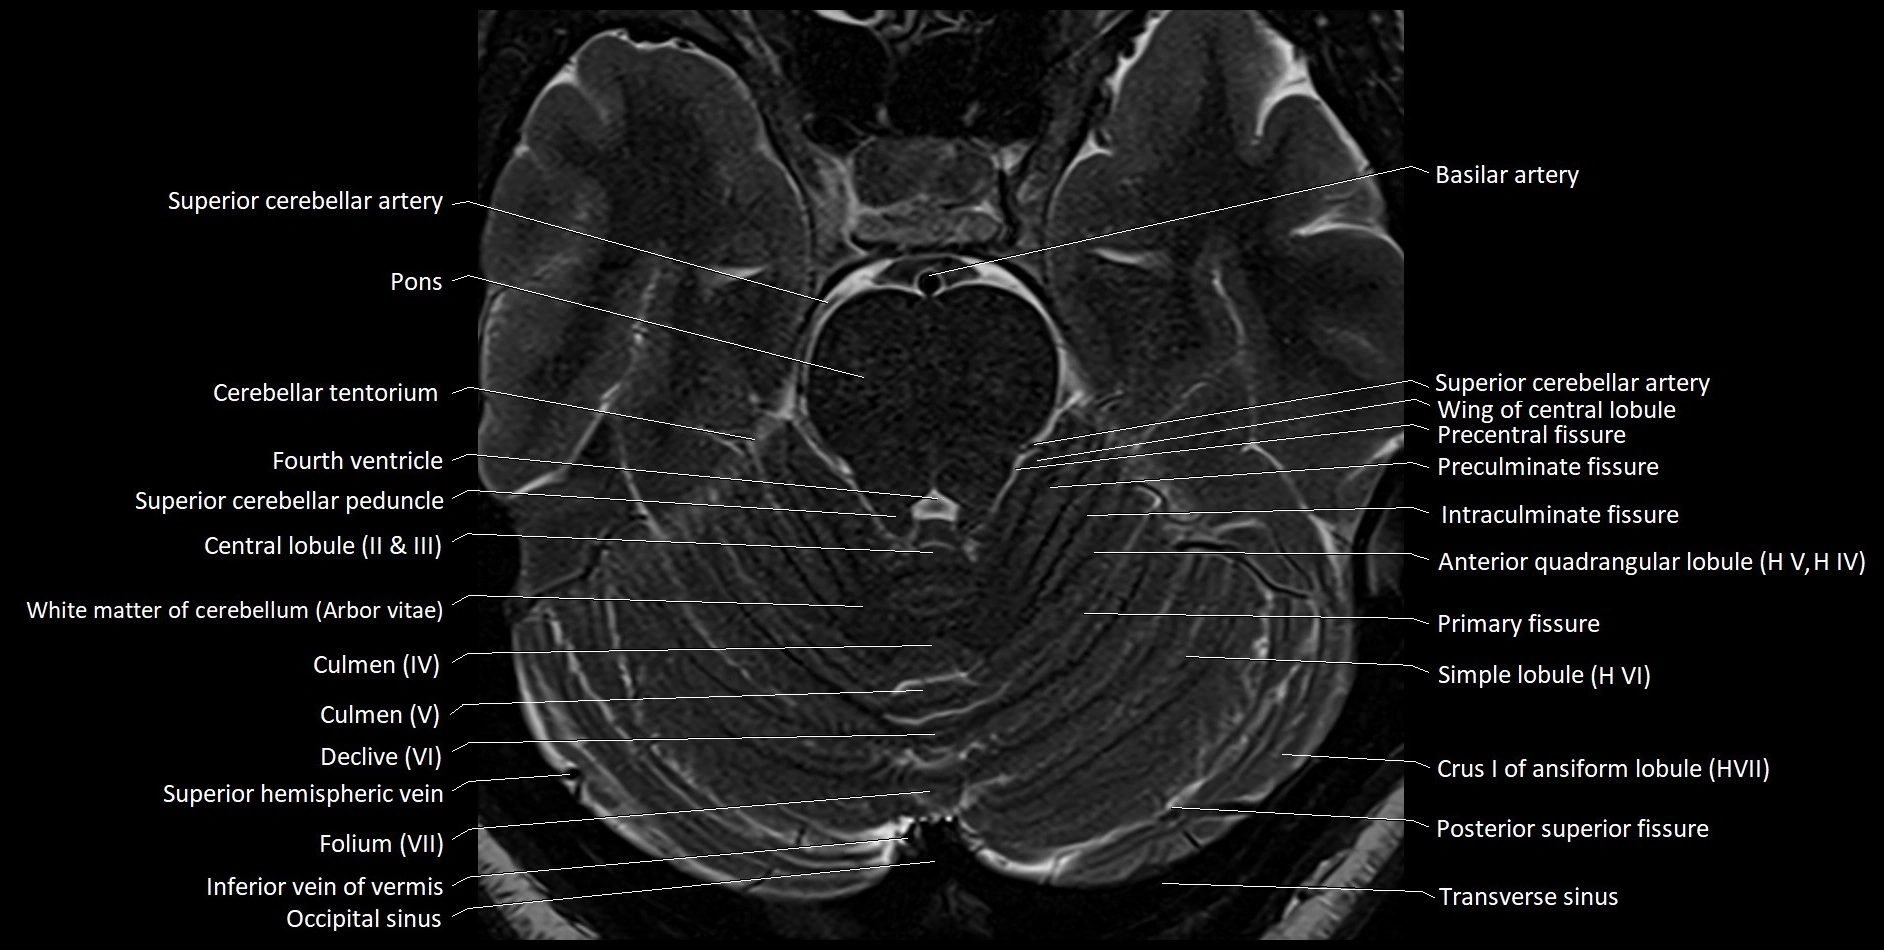

MRI images